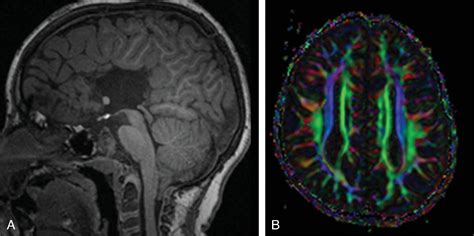

MRI (Magnetic Resonance Imaging) Detailed brain visualization High, provides the most accurate view.

The concept of neuroplasticity is perhaps the most hopeful aspect of managing this condition. Research suggests that when the corpus callosum is absent, the brain often develops "Probst bundles," which are bundles of nerve fibers that run longitudinally rather than crossing the midline. This allows the hemispheres to maintain some level of communication. Furthermore, the anterior and posterior commissures—smaller structures that connect the brain hemispheres—may enlarge to take on a larger share of the workload.

• corpus callosum agenesis mri